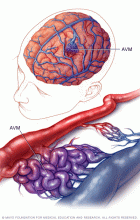

In a brain AVM, blood passes directly from the arteries to the veins via tangled vessels. This disrupts the typical process of how blood circulates through the brain.

In a brain arteriovenous malformation, blood passes directly from arteries to veins through a tangle of blood vessels.

A brain arteriovenous malformation (AVM) is a tangle of blood vessels that creates irregular connections between arteries and veins in the brain.

Arteries take oxygen-rich blood from the heart to the brain. Veins carry oxygen-depleted blood back to the lungs and heart. A brain AVM disrupts this vital process.

An arteriovenous malformation can develop anywhere in the body, but common locations include the brain and spinal cord. Overall, brain AVMs are rare.

In an arteriovenous malformation (AVM), blood passes quickly from the arteries to the veins, disrupting the typical blood flow and depriving the surrounding tissues of oxygen.

Typically, the heart sends oxygen-rich blood to the brain through arteries. The arteries slow blood flow by passing the blood through a series of smaller and smaller blood vessels. The smallest blood vessels are called capillaries. The capillaries slowly deliver oxygen through their thin, porous walls to the surrounding brain tissue.

The oxygen-depleted blood passes into small blood vessels and then into larger veins. The veins return the blood to the heart and lungs to get more oxygen.

The arteries and veins in an AVM lack this supporting network of smaller blood vessels and capillaries. Instead, blood flows quickly and directly from the arteries to the veins. When this happens, surrounding brain tissue doesn't receive the oxygen it needs.